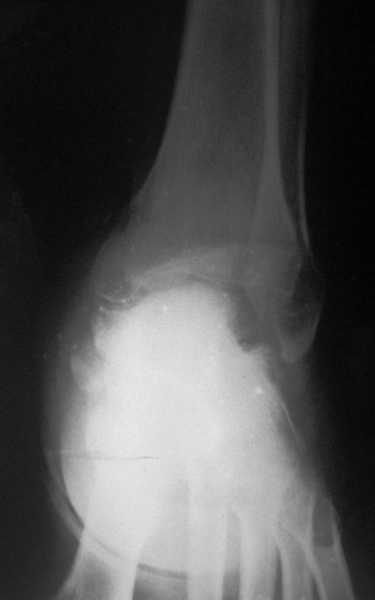

Глубокоуважаемые коллеги! Просим совета в лечении пациента с последствиями тяжелой сочетанной травмы. Пациент С., 41 года, по профессии бизнесмен, в сентябре 2005 г. пострадал в дорожно-транспортном происшествии (упал с мотоцикла). Диагноз: ЗЧМТ, ушиб головного мозга тяжелой степени. Открытый переломо-вывих левой таранной кости. Закрытые переломы лонной и седалищной костей слева. Был доставлен в НИИСП им. Н.В. Склифосовского. При ПХО раны выявлен открытый перелом левой таранной кости (III тип по Hawkins) с утратой вывихнутого тела таранной кости. Выполнена ПХО, фиксация голени и стопы стержневым аппаратом. Рана зажила без осложнений. Аппарат демонтирован через 1,5 месяца. В настоящее время больной предъявляет жалобы на боль в голеностопном суставе при нагрузке. Передвигается с опорой на костыли с дозированной нагрузкой на левую стопу.Голень и стопа фиксированы циркулярной пластиковой повязкой. Сохраняются остаточные явления ЧМТ (в виде сниженной критики к своему состоянию и определенной недисциплинированности в выполнении врачебных рекомендаций) Рентгенограммы – рис. 1, 2 (просим извинения за низкое качество рентгенограмм), схема – рис. 3. В качестве варианта хирургического лечения мы считаем возможным выполнить следующее вмешательство: артродез большеберцовой и пяточной костей в сочетании с артродезом переднего края большеберцовой кости и головки таранной кости с фиксацией спонгиозными винтами. Считаем выполнение артродеза переднего края большеберцовой кости и элементов I луча стопы необходимым для максимального восстановления опороспособности конечности. Однако выполнение операции в указанном объеме привело бы к относительному укорочению внутреннего свода стопы. Мы видим два пути решения данной проблемы: Вариант 1. Применение костного трансплантата (свободного или на сосудистой ножке) для замещения дефекта головки таранной кости и сохранения геометрии внутреннего свода стопы (рис 4). Преимущество: относительная простота операции. Недостаток: высокий риск замедленной консолидации или лизиса трансплантата. Вариант 2. Резекция участка пяточной кости с последующим остеосинтезом винтами для укорочения наружного свода стопы (рис 5, 6). Преимущества: сохранение собственного кровоснабжения всех синтезируемых участков костей. Недостатки: дополнительная травматизация, усугубление деформации стопы в виде нарушения наружного свода. Будем признательны за ваши предложения, включая возможные альтернативные варианты лечения.Заранее благодарны за добрые советы и поддержку. А. Федосов, О. Диденко, П. Иванов. Отделение множественной и сочетанной травмы НИИСП им. Н.В. Склифосовского, г. Москва.